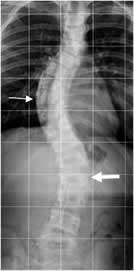

Después de un amplio recorrido desde la pelvis-sacro, a la cabeza-nuca; o,

desde los pies, el sentimiento de la persona es completamente diferente y los

dolores, que ya se habían corregido con la osteopatía estructural, visceral a

veces también, y craneal, con la técnica de liberación somato-emocional, (en

fotografías anteriores), la carga y presión interna desparecen, ¡literal!

Son

sesiones profundamente de intercambio materia-energía, de bloqueo-movimiento,

con una base y un fondo puramente científico, de estudio. Son sesiones tan

placenteras como esto que te enseño a continuación.